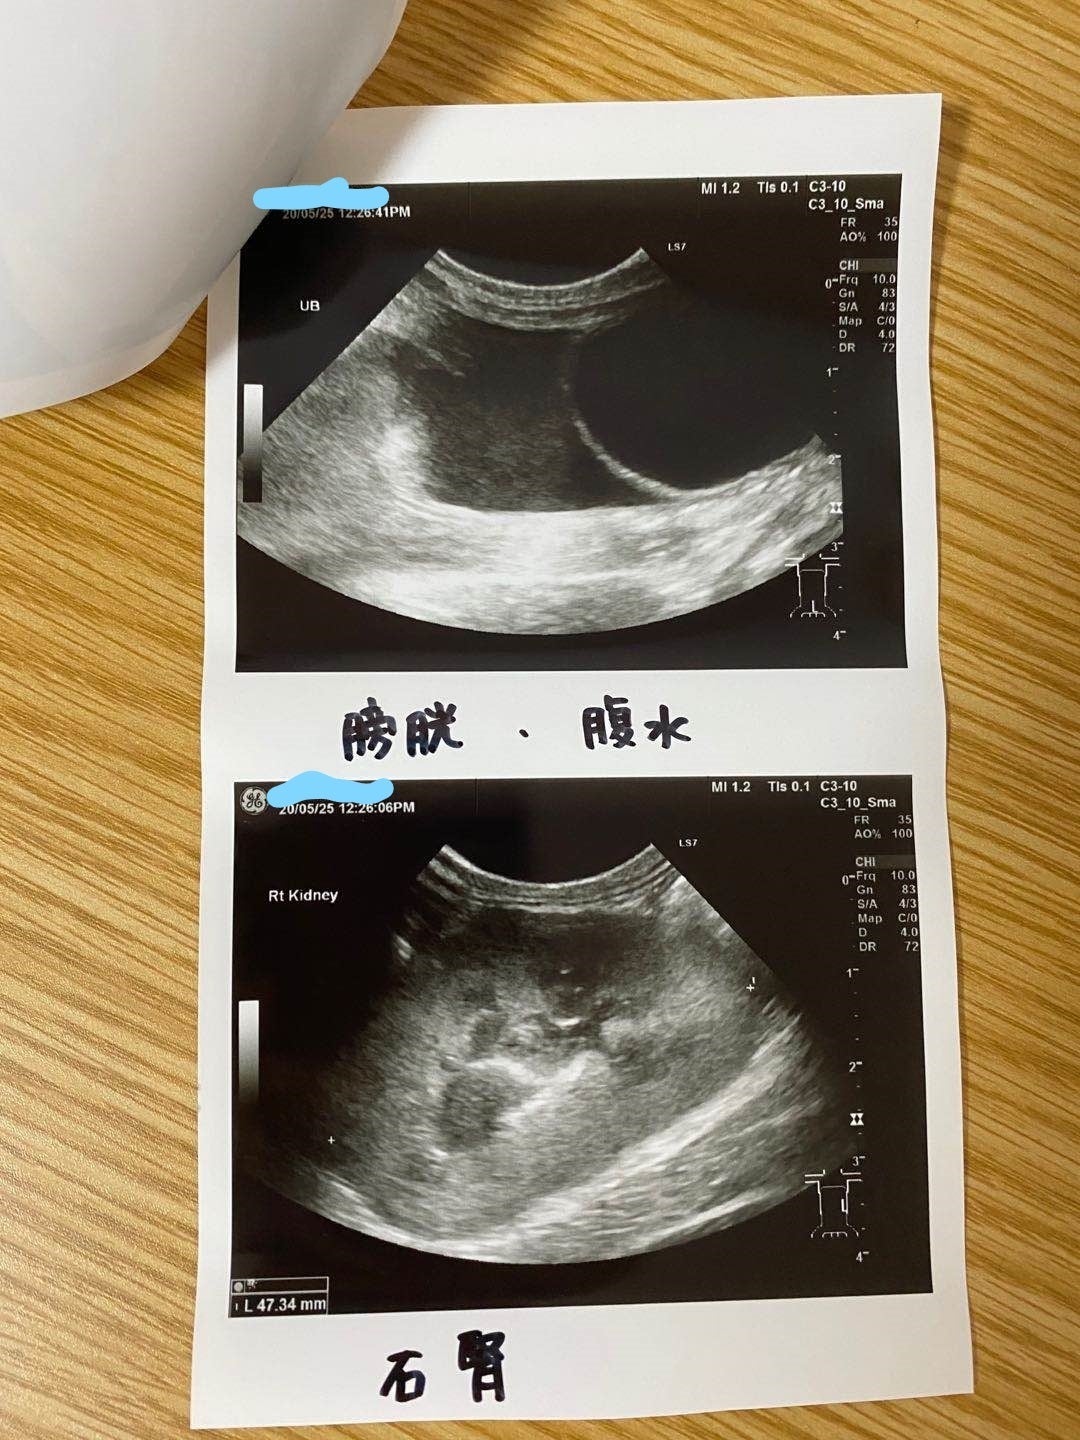

5/25家の近くの協力病院に行って、痛く辛い検査をして、中期混合型と診断されました。

腹水がたまっています

肉芽腫が見つかります

39℃の熱と重度の貧血もあります

強い炎症もあります